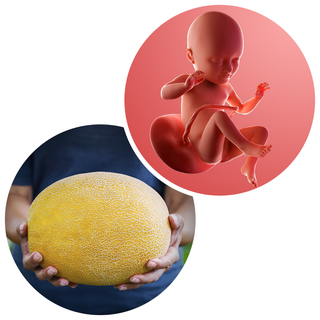

What does my baby look like?

Your baby, or foetus, is around 45cm long from head to heel. That's approximately the size of a cantaloupe melon.

Your baby is curled up inside your uterus (womb), with their little legs bent up towards the chest.